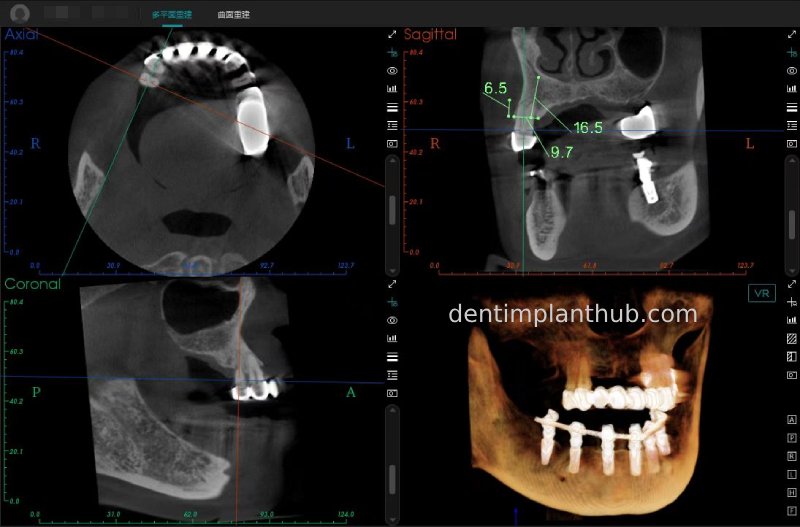

Maxillary condition as shown by CBCT on 13/5/24

16

14

12

22

24

26

Details of implant sites, protocols, implant types, composite abutments, 13.5.24

16, implant model 4810, requires an internal elevation of the maxillary sinus floor and an RC series straight composite abutment;

14, implant model 4812, requires an RC series 15° composite abutment;

12, implant model 4112, requires an RC series 30° composite abutment;

22, implant model 4112, requires an RC series 30° composite abutment;

24, implant model 4812, requiring an RC Series 15° composite abutment;

26, implant model 4810, requiring an internal maxillary sinus floor lift, requiring an RC Series straight composite abutment;